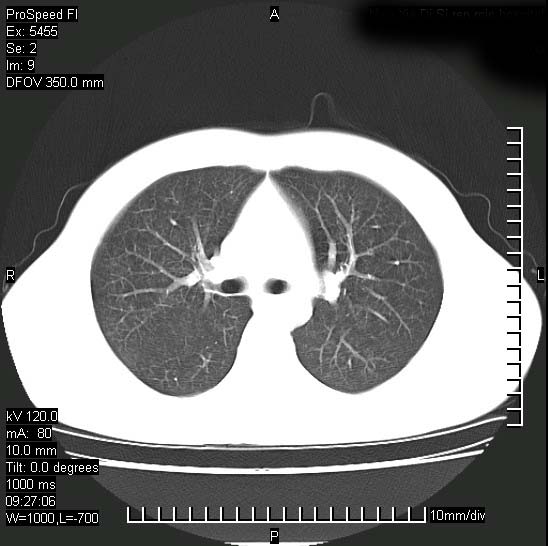

以下是引用zjzjr在2008-12-3 20:50:00的发言:[br]考虑泛细支气管肺炎,建议进一步检查除外肺出血性疾病如含铁血黄素沉着症、肺肾综合征等。

以下是引用zjzjr在2008-12-3 20:50:00的发言:[br]考虑泛细支气管肺炎,建议进一步检查除外肺出血性疾病如含铁血黄素沉着症、肺肾综合征等。

以下是引用光线在2008-12-3 20:19:00的发言:[br]双肺间质性改变。